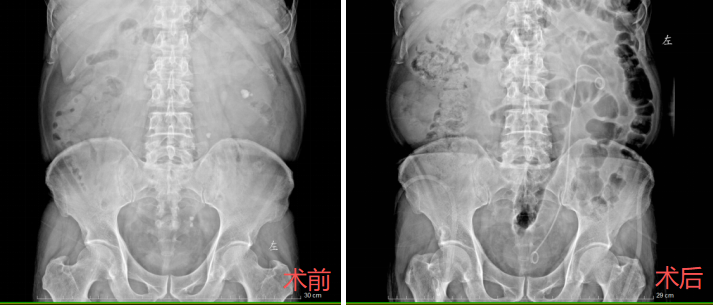

家住钟家村的吴先生因左侧腰腹疼痛,前来武汉市第五医院就诊。经详细检查,确诊为左侧输尿管中段多发结石,其中最大一颗直径约6.5毫米,同时伴有左肾多发结石,最大者直径约15毫米。由于结石负荷较大且分布散乱,手术清石难度较高。泌尿外科团队为患者制定个体化微创方案,并由李京涛医师主刀实施手术。